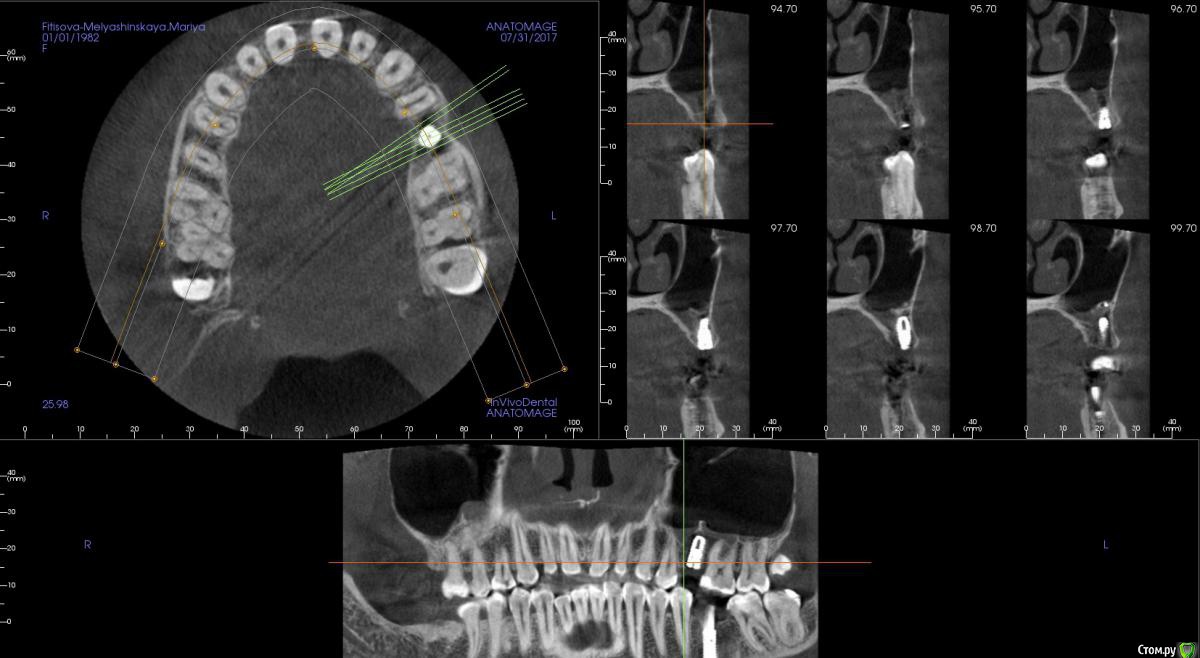

kamranchick Опубликовано 31 июля, 2017 Автор Поделиться Опубликовано 31 июля, 2017 Как то вот так получилось Ссылка на комментарий

Bobon Опубликовано 31 июля, 2017 Поделиться Опубликовано 31 июля, 2017 длина 8,5? Ссылка на комментарий

kamranchick Опубликовано 31 июля, 2017 Автор Поделиться Опубликовано 31 июля, 2017 длина 8,5?ага Ссылка на комментарий